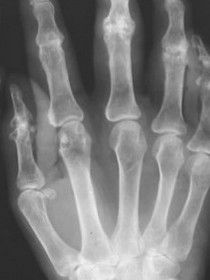

任張志毅教授介紹,風關痛迄今原因不明,以風、寒、濕環境因素及體力負荷為主要危險因子,以膝、腰椎等多關節疼痛為主要臨床表現。這種關節痛,只有關節疼

痛症狀,無腫脹等炎性體徵,實驗室檢查及放射學診斷均無異常。雖然風關痛可以視為無病或是一種特殊的生理現象,但通過動物模型及患者組織病理學研究,發現

其仍存在一定的微循環、炎症介質、軟骨代謝等病理學改變。風關痛巨觀上呈良性經過,不致殘,不危及生命,因而很少有人系統研究。在祖國醫學中,本病被視之為痹症,早在兩千年前《素問·痹論》中就有“風、寒、濕三氣雜至,合而為痹也”的記載。其後歷代醫家在此基礎上對痹症的認識不斷豐富和發展,認為痹症的發病是由於身體虛弱,陽氣衛外不固,風、寒、濕乘虛而入,留於肌肉、經絡、關節,引起氣血痹阻,運行不暢,由此發生疼痛、酸麻、沉重及伸屈不利等表現。